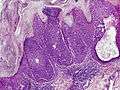

An eccrine poroma specifically refers to a tumor derived specifically from the most apical portion of eccrine sweat gland (acrosyringium). They are most commonly found on acral distribution (on palms & soles), and most commonly in adults. They are described as <1–2 cm pink/red shiny, exophytic lesions that can be pigmented and are clinically very similar to pyogenic granulomas.[3] Histologically, the cells as PAS-positive and clearly surrounded by normal keratinocytes. These tumors are surgically excised usually without complication or recurrence, although malignant porocarcinomas can recur and metastasize to local lymph nodes.[4]